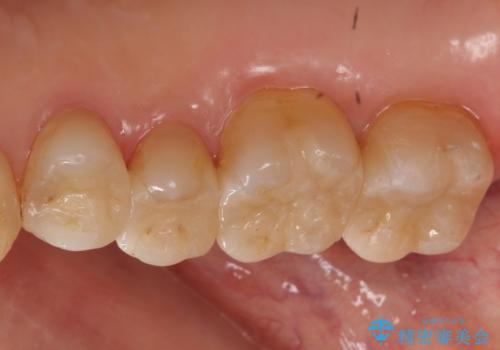

銀歯を白く 虫歯治療

- 虫歯治療を希望して来院。

保険適用の銀色のつめもののやり替えを行いました。

- 30.8万円(右上4567 emaxプレスインレー 7万円x4本)費用は治療当時の料金となります